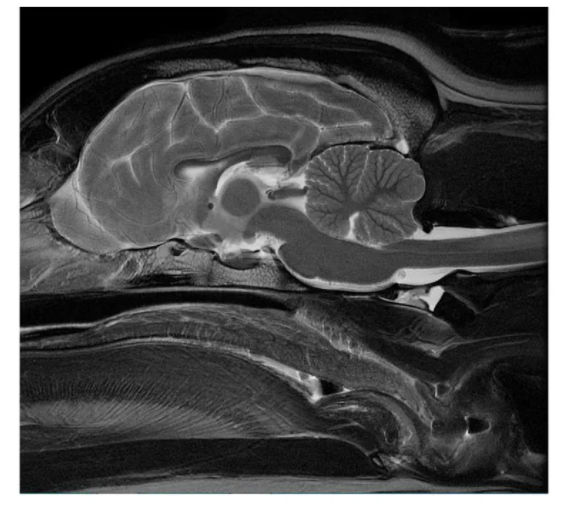

МРТ в ветеринарии🔮

Для начала определимся, что мы видим на МРТ-снимках.

Такая технология позволяет точно оценить состояние мягких тканей, хрящей, мозга, органов, дисков позвоночника, связок, дифференцировать одни ткани от других, а также выявлять всевозможные отклонения от нормального строения организма - новообразования, смещения, деформации межпозвоночных дисков и т.д.

Помимо контраста, который может использоваться при проведении процедуры (он позволяет исследовать циркуляцию жидкости и увидеть места аномального накопления жидкости), существует несколько "режимов", в которых мы можем получить снимки. Это необходимо для более корректного и подробного анализа снимка. В зависимости от режима изменяется контрастность той или иной структуры.

А еще, МРТ - это красиво. И порой забавно. Вот вам мопс, например: